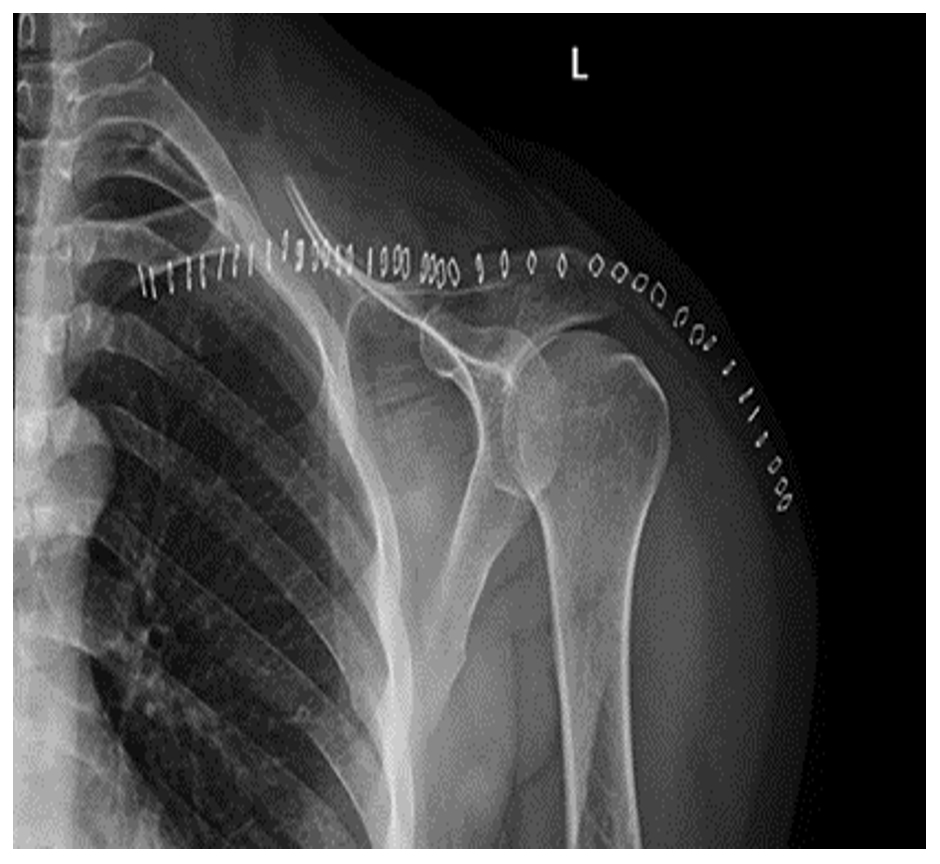

Ameliyat Sonrası: Röntgende kısmi klavikula, corocoid ve acromion eksizyonu yapıldığı görülmekte.